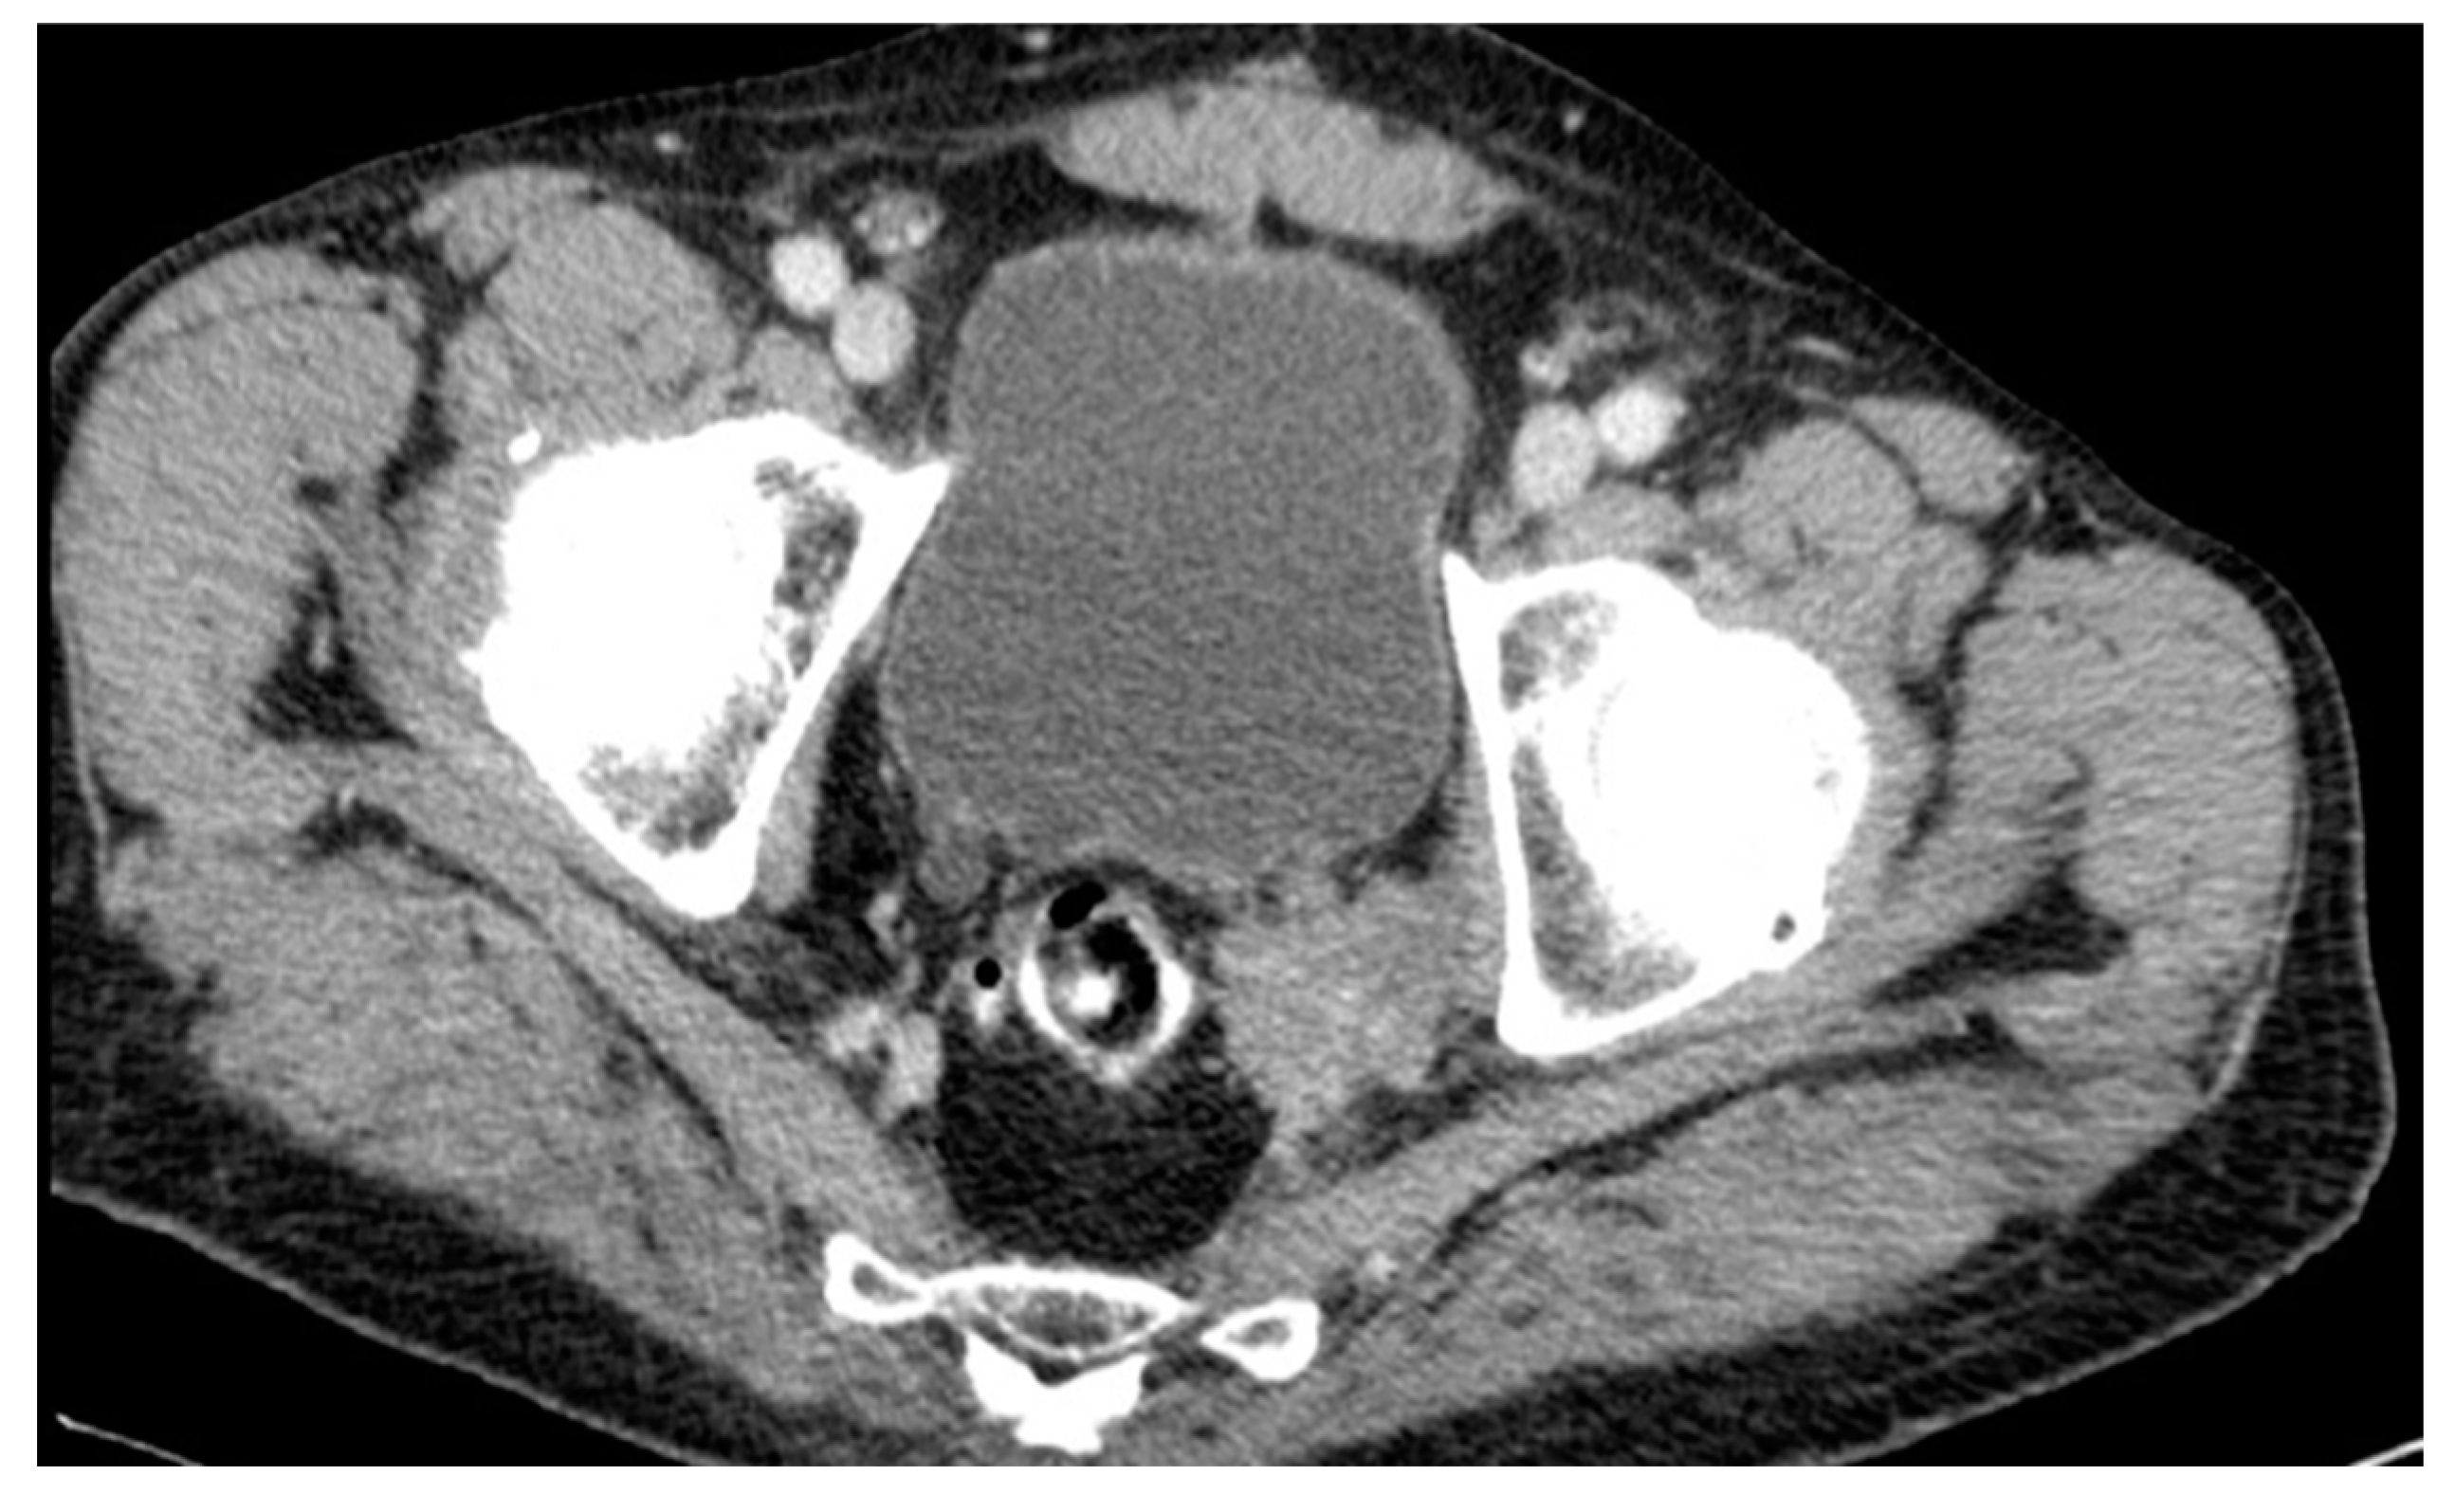

| 50 years | Female | ypT3ypN2a | 6 months | Lateral/nodal |

| 76 years | Male | ypT2ypN1 | 135 months | Lateral/nodal |